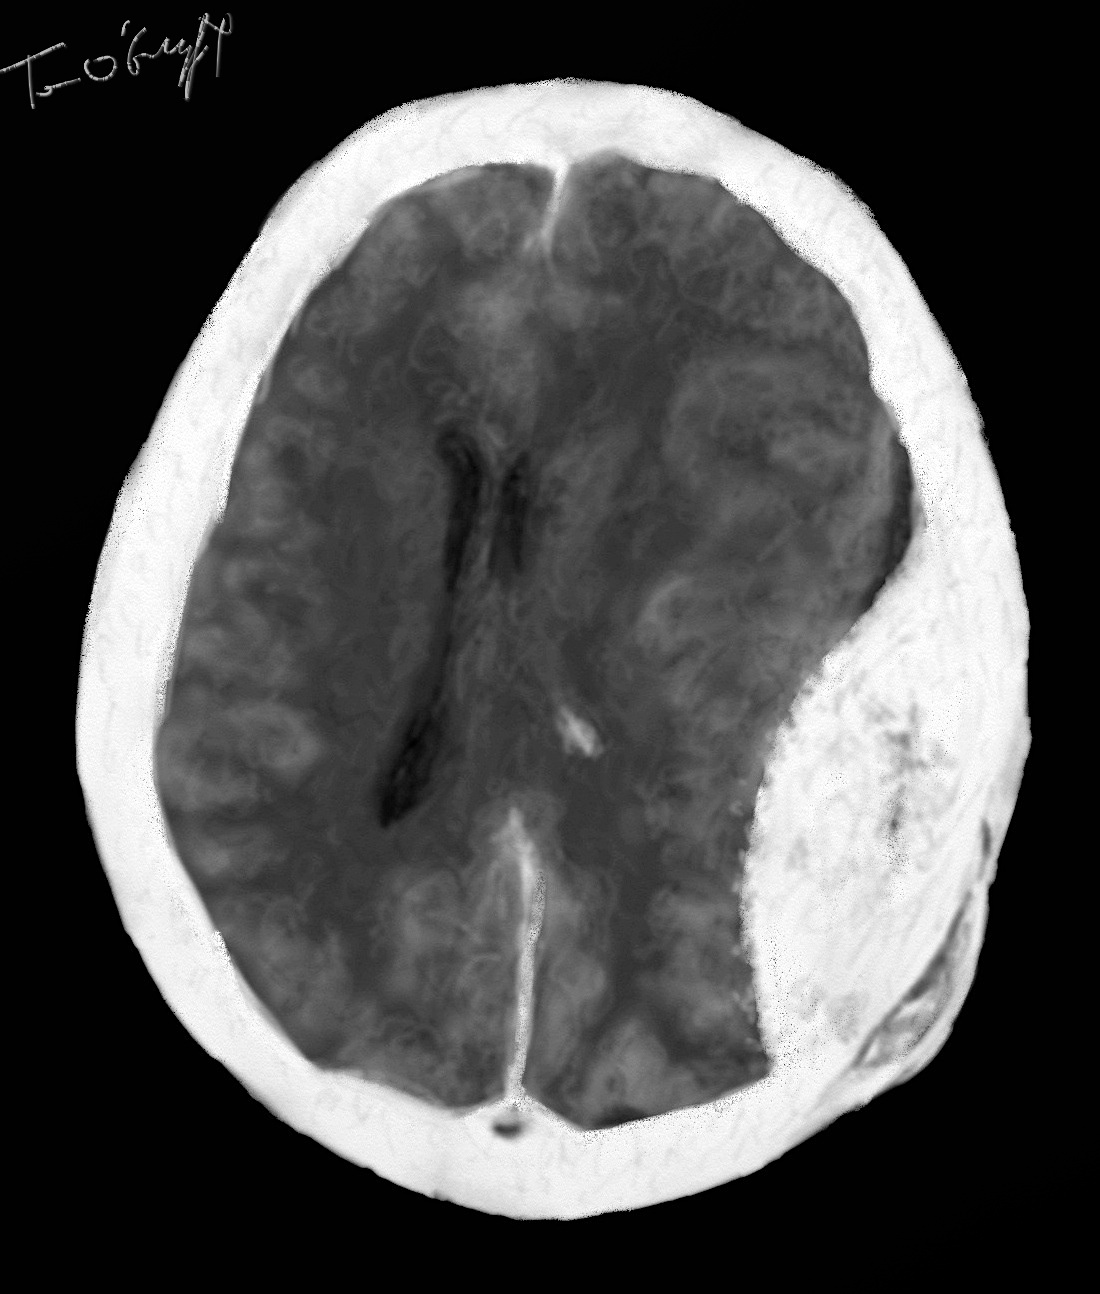

hématome extradural droit de grand volume avec déplacement des structures médianes, scanner cérébral

Le scanner fait le diagnostic en une image d’hyperdensité (donc blanche)sous forme de lentille biconvexe, ce qui donne donc un bombement convexe vers le cerveau. Classiquement homogène hyperdense, l’aspect peut être plus discret au niveau couleur dans un premier temps, dans un HED vu tôt. L’aspect est parfois beaucoup plus hétérogène voire de même densité que le cerveau avec une zone d’hémorragie active hyperdense. C’est exceptionnel mais la survenue de 2 hématomes extra duraux en 2 localisations opposées est possible et de façon retardée.

Si l’hématome est important, la compression sur le cerveau efface les sillons corticaux du côté de l’hématome, écrase les ventricules latéraux, va même jusqu’à refouler les structures homolatérales de l’autre côté avec un engagement sous la faux du cerveau. L’engagement dans la tente du cervelet ou le tronc cérébral est plus difficile à mettre en évidence au scanner.